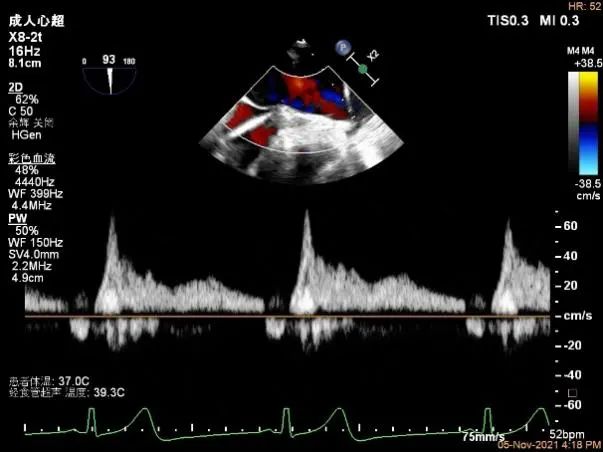

右上肺静脉血流频谱呈收缩期反向

肺静脉血流频谱恢复正向

(4)架子释放后,返流较释放前略加重,验证了上述器械的设想。但反复评估后为微少量返流,肺静脉频谱恢复正常。X线和超声下看夹子稳定,活动度不大。最终未置入第二枚MitraClip。